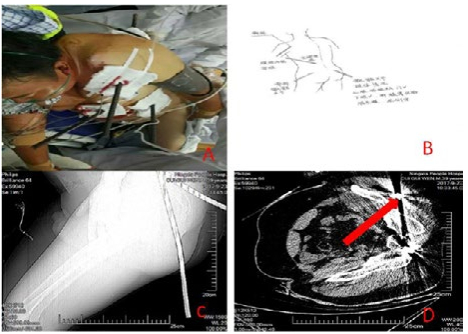

1 资料与方法患者男,39岁,于2017年9月23日在建筑工地作业时不慎从7 m高处坠落,致全身被多根钢筋贯通伤,伤后即感全身疼痛,呼吸困难,神志清楚,经消防人员初步处理后由我院院前人员给予初级创伤救治,通知院内启动应急预案系统。入院后查体血压88/60 mmHg(1 mmHg=0.133 kPa),脉搏110次/min,R 20次/min,血氧饱和度95%,神清,面色及睑结膜苍白,强迫左侧卧位,可见1根钢筋(长约50 cm)自左肩胛区左前胸部,三根钢筋分别自左臀部至左肩部贯通,右臀部至上腹部贯通,左腰部贯通左上腹(图 1),伤口出血不止,呼吸活动左右不一致,左肺呼吸音减弱,右肺呼吸音清晰,四肢活动尚可,腹部压痛及反跳痛查体不配合。实验室检查WBC 12.66 ×109/L;其余化验结果均正常。腹部B超示:①右肝、胰腺显示不清;②脾周少量积液,深约1.2 cm,因伤者身上横着钢筋,无法以正常体位CT扫描,初步诊断为“胸腹部钢筋贯通伤;创伤性休克”。患者影像学资料见图 1。

| A:患者入院情况;B:手绘图;C、D:影像学检查结果 图 1 患者资料 |